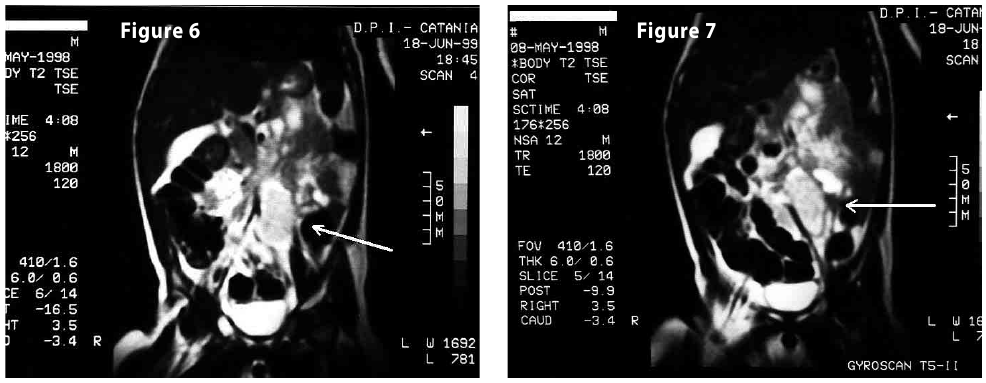

Figure7

Figure6-7